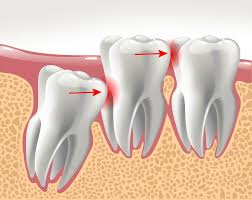

How To Tell If You Have Impacted Wisdom Teeth : Grow at a right angle to the other teeth, as if the wisdom tooth is lying down within the jawbone 4.

Tender or bleeding gums 3. What you should know about an impacted wisdom tooth? Some dentists and oral surgeons also recommend removing impacted wisdom teeth that don't cause symptoms to prevent future problems. An impacted wisdom tooth may partially emerge so that some of the crown is visible (partially impacted), or it may never break through the gums (fully impacted). Damage to other teeth.if the wisdom tooth pushes against the second molar, it may damage the second molar or increase the risk of infection in that area. Ignoring headaches or jaw pain will only allow the condition to advance. This complication may require removal of tissue and bone. This probably occurs because wisdom teeth are harder to clean and because food and bacteria get easily trapped between the gum and a partially erupted tooth.

Whether partially or fully impacted, the tooth may:

Some dentists and oral surgeons also recommend removing impacted wisdom teeth that don't cause symptoms to prevent future problems. See full list on mayoclinic.org Damage to other teeth.if the wisdom tooth pushes against the second molar, it may damage the second molar or increase the risk of infection in that area. See full list on mayoclinic.org When they are impacted, it means the teeth either become stuck under the gum or are only able to partially break through the gum. In many cases, however, the mouth is too crowded for third molars to develop normally. Causes & risks · signs & symptoms · healthprep official Impacted wisdom teeth can result in pain, damage to other teeth and other dental problems. Wisdom teeth often can't grow in normally. Ignoring headaches or jaw pain will only allow the condition to advance. How serious is your impacted wisdom tooth? Healthprep.com has been visited by 100k+ users in the past month Grow straight up or down like other teeth but stay trapped within the jawbone

When they are impacted, it means the teeth either become stuck under the gum or are only able to partially break through the gum. In many cases, however, the mouth is too crowded for third molars to develop normally. Grow at a right angle to the other teeth, as if the wisdom tooth is lying down within the jawbone 4. Often it will pop up through one day and go down the next. Causes & risks · signs & symptoms · healthprep official Impacted wisdom teeth may also be coming through the gums a little. This complication may require removal of tissue and bone. Options for treating impacted teeth.

Grow straight up or down like other teeth but stay trapped within the jawbone May 18, 2017 · the symptoms caused by impacted wisdom teeth in palm harbor, fl, will not simply go away without treatment. How serious is your impacted wisdom tooth? Impacted wisdom teeth can cause several problems in the mouth: Options for treating impacted teeth. However, when an impacted wisdom tooth becomes infected, damages other teeth or causes other dental problems, you may experience some of these signs or symptoms: See full list on mayoclinic.org Unfortunately, for those who do not have sufficient space for them to grow in properly, they can create a slew on oral health problems that may linger on indefinitely. This probably occurs because wisdom teeth are harder to clean and because food and bacteria get easily trapped between the gum and a partially erupted tooth. Wisdom teeth often can't grow in normally. In some cases, impacted wisdom teeth may cause no apparent or immediate problems. Wisdom teeth usually emerge sometime between the ages of 17 and 25. Healthprep.com has been visited by 100k+ users in the past month

They may also push the neighboring teeth out of place. Grow at an angle toward the next tooth (second molar) 2. Wisdom teeth often can't grow in normally. In some cases, impacted wisdom teeth may cause no apparent or immediate problems. See full list on mayoclinic.org